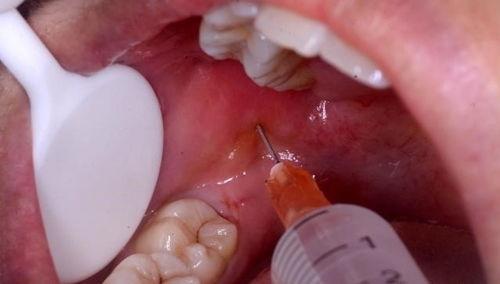

别急,让我带你一探究竟。在拔智齿的视频中,你可以看到医生们是如何使用专业的工具,小心翼翼地分离智齿与牙槽骨的连接。他们会用牙挺、牙钳等工具,将智齿从牙槽骨中拔出。整个过程看似简单,但实际上需要医生们丰富的经验和精湛的技艺。

在这些视频中,你还可以看到医生们是如何处理拔除后的伤口。他们会用盐水冲洗伤口,确保没有残留的细菌。他们会给你戴上牙套,防止伤口感染。